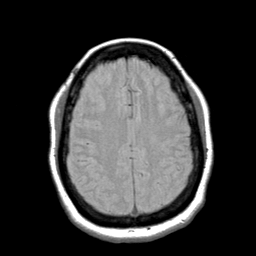

Cerebral hemorrhage, MR Study mr-pd -- Slice #17

[Home][Help][Clinical] Slice 17